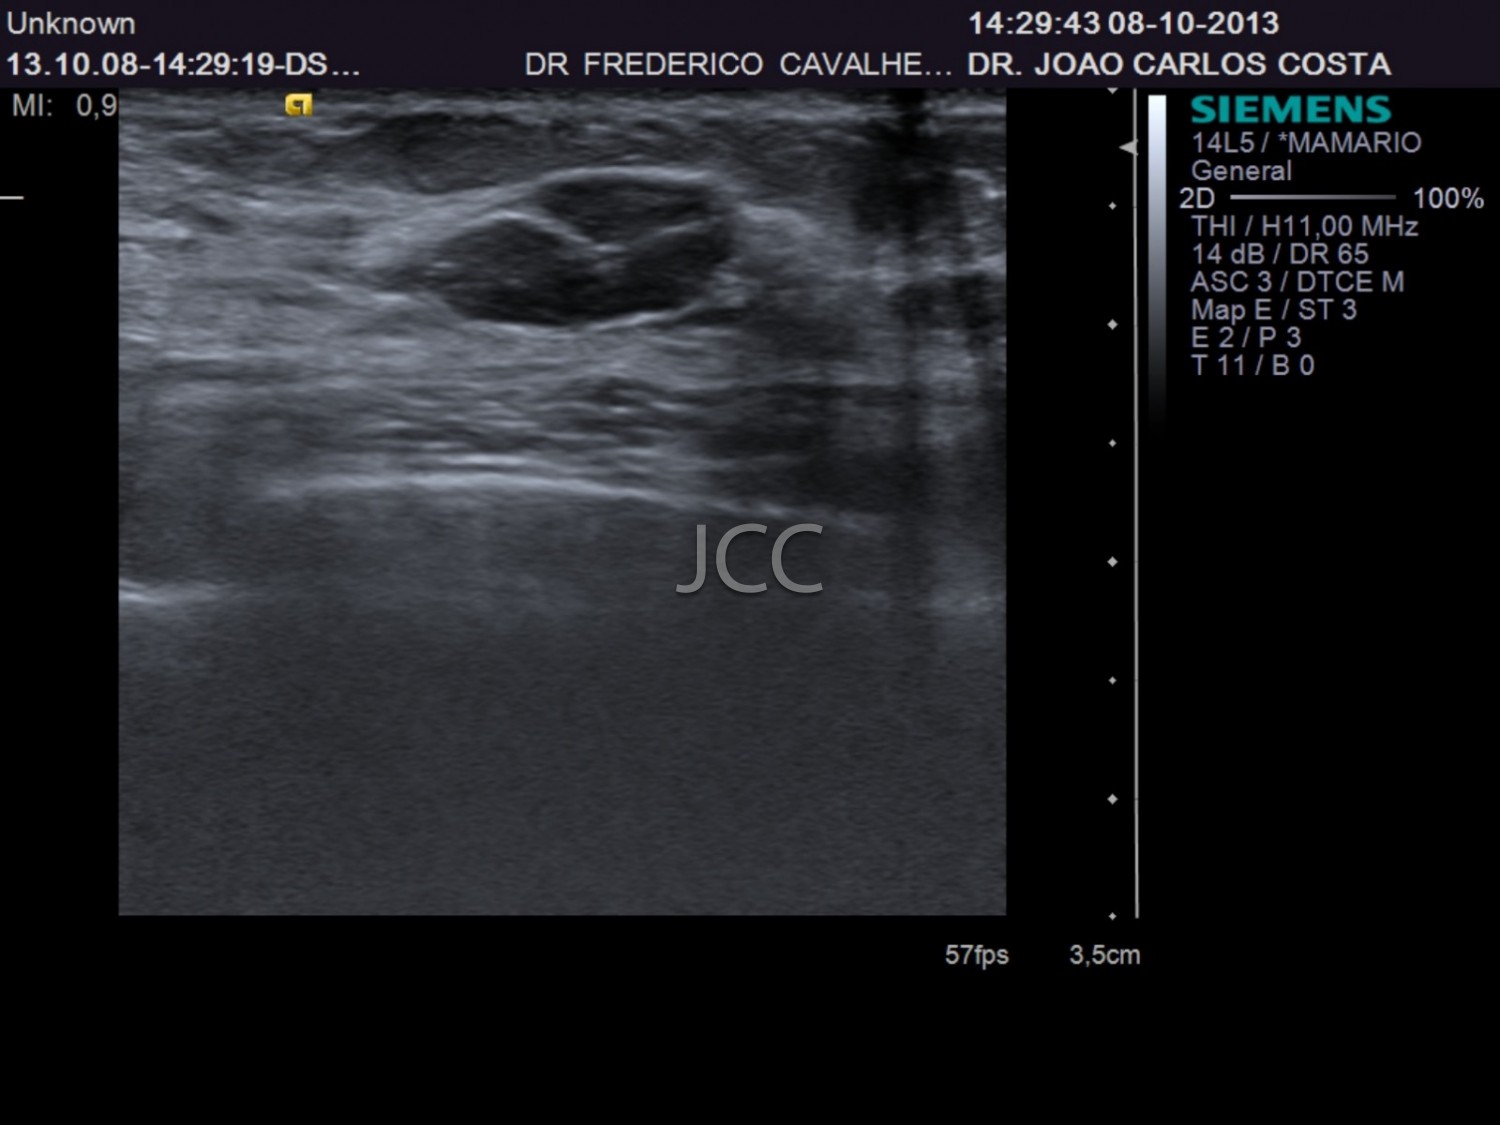

Ecografia - Biópsia por ecografia

A Ecografia constitui um método mais acessível permitindo de modo simples e rápido a avaliação dos órgãos do corpo humano incluindo o fígado, vias biliares, vesícula, pâncreas, rins, bexiga e próstata, bem como órgãos de menores dimensões como a tiróide, parótidas e estruturas musculares.

Constitui uma óptima técnica para guiar a realização de biópsia. Quando associada ao Doppler permite o estudo das estruturas vasculares arteriais e venosas de modo dinâmico.